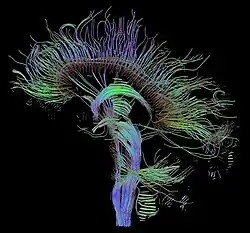

Tractography of human brain | |

In neuroscience, tractography is a 3D modeling technique used to visually represent nerve tracts using data collected by diffusion MRI.[1] It uses special techniques of magnetic resonance imaging (MRI) and computer-based diffusion MRI. The results are presented in two- and three-dimensional images called tractograms.[2]

This additional information is difficult to represent on 2D grey-scaled images. To overcome this problem, a color code is introduced. Basic colors can tell the observer how the fibers are oriented in a 3D coordinate system, this is termed an "anisotropic map". The software could encode the colors in this way:

- Red indicates directions in the X axis: right to left or left to right.

- Green indicates directions in the Y axis: posterior to anterior or from anterior to posterior.

- Blue indicates directions in the Z axis: inferior to superior or vice versa.